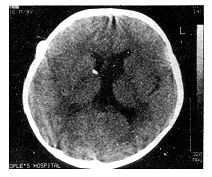

摘要 目的:研究治疗囊性颅咽管瘤最佳治疗方法。方法:对34例囊性颅咽管瘤进行CT立体定向囊腔内胶体磷酸铬内放疗。结果:全部病例经手术排除囊液后临床症状迅速改善,经囊腔内放疗后12~66个月随访,CT扫描显示28例(82.5%)瘤腔持续消失,3例(8.8%)瘤腔显著缩小,症状持续改善。3例(8.8%)分别于19、25、36个月后因瘤实质部分增大,症状恶化而相继死亡。无手术死亡率和严重并发症。结论:CT立体定向囊腔内放疗治疗囊性颅咽管瘤十分安全、有效,应作为治疗囊性颅咽管瘤首选的方法。

Abstract Objective: To investigate the value of sterotatic intracavitary irradiation for cystic craniopharyngiomas. Methods: Thirty-four patients with cystic craniopharyngiomas were treated with CT-guided stereotatic intracavitary irradiation with 32 P in a colloidal solution. Results: The clinical symptoms improved promptly after evacuations of cyst in all patients. No mortality or severe complications. Follow-up (ranged from 12 to 66 months) CT indicated the tumor cysts gradually regressed and disappeared in 28 cases (82.5%), decreased obviously in 3 cases (8.8%). However, other 3 patients died at the 19th, 25th and 36th month after operation because of the increasing solid parts of tumors. Conclusions: CT-guided stereotactic intracavitary irradiation for cystic craniopharyngioma is safe and effective, it should be the most appropriate initial surgical management.